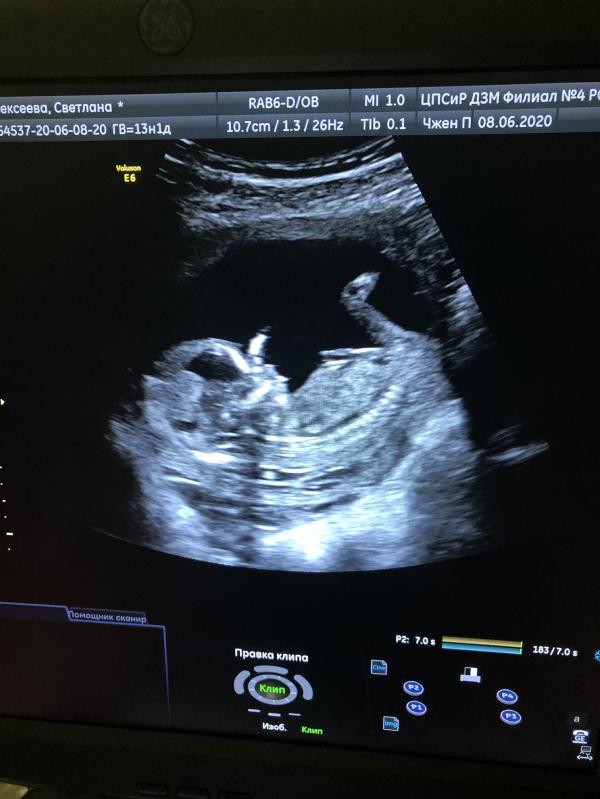

Мы вот впервые увиделись с малышом🥰

Какие то непередаваемые эмоции конечно 😍по узи все хорошо, жду показатели крови , надеюсь и там все отлично 👍🏼